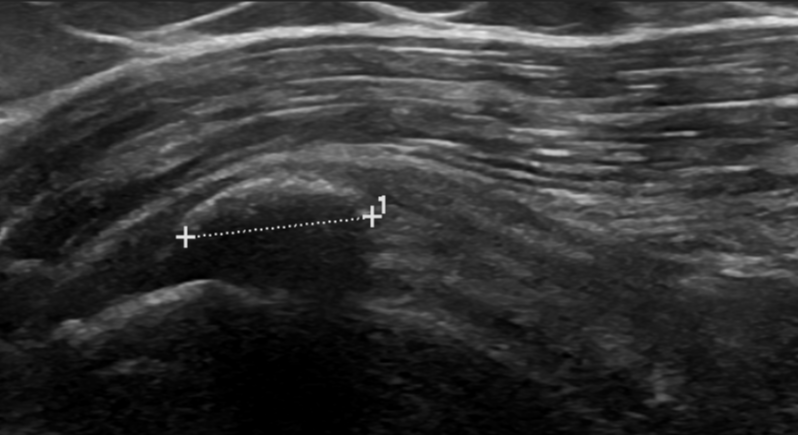

3. Calcific tendinopathy of supraspinatus